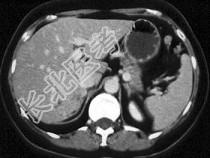

- 单项选择题根据所提供的图像,可除外下列哪种诊断 ( )

A、血管瘤

B、局灶性结节增生

C、肝脏腺瘤

D、肝癌

E、以上都不是